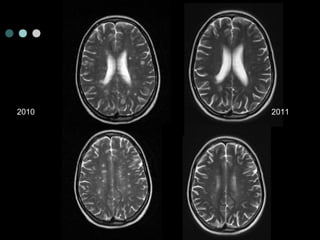

2010 2011

Natalizumab: good things AFFIRMHighly Active* 1 (n= 148 for TYSABRI, 61 for PBO) 81% 64% reduction in annualised relapse rate vs. placebo over 2 years (p < 0.001) reduction in the risk of disability progression, sustained for 24 weeks, as assessed over 2 years (p =0.008) Patients With ≥2 Relapses in Prior Year and ≥1 Gd+ Lesion At Baseline